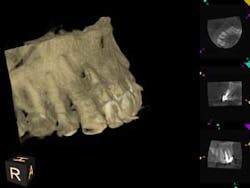

A 52-year-old male patient presented to the office with pain related to tooth No. 9. After radiographic review (figure 4), it was noted that No. 9 had previous endodontic therapy along with a large cast post. The patient was happy with the esthetics of the crown on No. 9, and the clinical and radiographic review showed intact margins and a sound restoration. The recommendation was made to take a narrow-field CBCT image of tooth No. 9. It revealed periapical pathology related to tooth No. 9 that had not broken through the buccal or palatal cortex (figure 5). No fractures were noted and disassembly of the current restoration was not ideal due to the size of the casting in place. The patient was appointed for microsurgical endodontic treatment to save tooth No. 9.

Again, a very minimal osteotomy could be made with the use of an operating microscope. After proper root resection, root-end prep, the placement of a biocompatible bioceramic filling (figure 6), the site is ready to be grafted. The lesion is removed and sent for biopsy, and we are left with a zero-degree bevel to root-end prep, and filling at this point becomes analogous to a Class I restoration. After radiographic verification that we have proper root resection and adequate apical fill, our bone grafting material was placed and final radiographs where taken (figure 7).